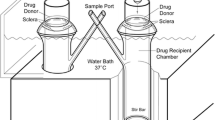

New Zealand white rabbit was the animal model and manganese ion (Mn2+) and manganese ethylenediaminetetraacetic acid complex (MnEDTA2−) were the model permeants. The current study was divided into three parts: in vitro, postmortem, and in vivo. Transscleral passive permeation experiments were conducted with excised sclera in side-by-side diffusion cells in vitro. Subconjunctival delivery experiments were conducted with rabbits postmortem and in vivo. The distribution and elimination of the probe permeants from the subconjunctival space after subconjunctival injections were determined by MRI.